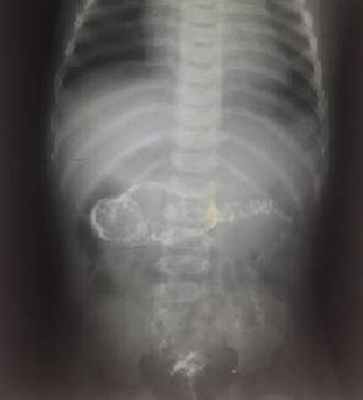

На рисунках 4 и 5 представлена картина кишечной инвагинации при рентгенологическом исследовании.

Рис. 5. Ирригограмма после опорожнения толстой кишки - симптом «кокарды»